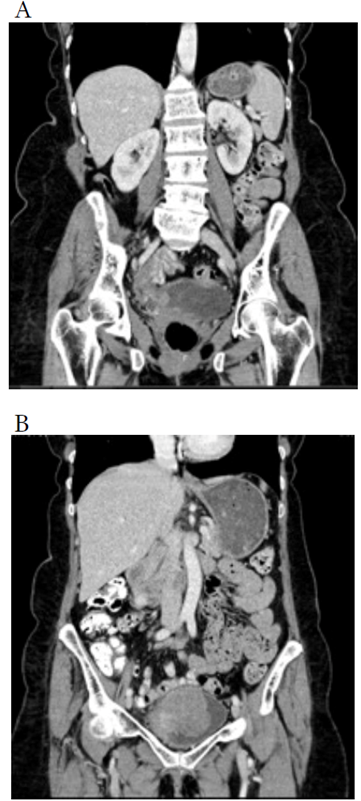

We aimed to describe the case of a woman diagnosed with concomitant primary small-cell neuroendocrine carcinoma and high-grade papillary urothelial. (Figure 1).

She was a 63-year-old woman with no history of exposure to toxic substances or previous pathologies. She came to the emergency room complaining of five months of unintended weight loss, hypogastric pain, mass sensation, and urinary storage symptoms: daily frequency, nocturia, urgency, and urgency urinary incontinence, and gross hematuria. She received non-steroidal anti-inflammatory drugs. Physical examination revealed cachexia and hypogastric tenderness associated with a palpable solid mass. Laboratory tests showed moderate anemia (hemoglobin 8.9 gr/dl, hematocrit 28.3 %), mild thrombocytosis (500.000/uL), and an elevated C-Reactive Protein (14.26 mg/dL) with no other abnormal values among ionogram, serum creatinine, or lipid profile. The abdominopelvic scan revealed an intravesical mass, measuring 63x70x71mm, compromising the anterior and superior bladder walls, infiltrating the muscular layer, associated with increased fat attenuation (Figure 1. A), and another 11 mm polypoid lesion at the posterolateral right wall. (Figure 1. B). Thorax and brain scans were negative for metastatic compromise.